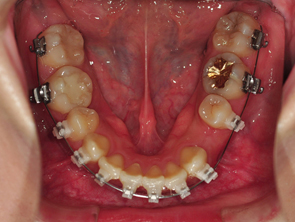

이번에 가니 상악 치아들중 발치해야 하는 부분을 알려주셨답니다. 그부분은 사진에보이는 뿌리만 남아있는 한곳과 대칭다는 반대편쪽 하나 각각 5번,5번 인 치아들이 었어요.,

하악 스크류 진행은 사진에 위치와 각 위치에 대해 설명을 넣어놓은것처럼 앞부분에 스크류를 넣는것이 가장 이상적이지만 치아를 발치한 부분이어서 잇몸이 약해 스크류를 넣기 힘들수도 있다고 하시더라구요 ㅠㅠ 그래서 그다음으로 후보2번째 에 스크류를 넣을 수도 있고 만약 후보2번에 안된다면 입안쪽으로 후보3번 부분에 해야하는데 그쪽은 잇몸을 절제해서 스크류를 진행해야 한다고 하시면서 잇몸 건강하죠~~?? 하시는 의사 선생님 후엉!! 제발~!!!!! 후보1번에 스크류 할수있었으면 좋겠어요 ㅠㅠㅠ